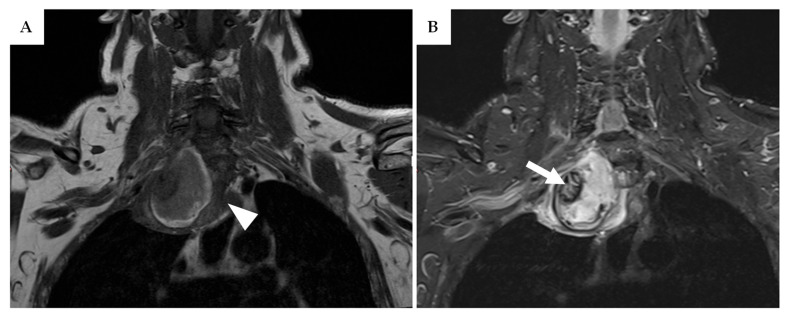

Background/Objectives: Peripheral nerve tumours are commonly encountered in clinical practice. Although most are benign, a subset can exhibit aggressive and invasive behaviour, evolving into malignant peripheral nerve sheath tumours (MPNSTs). Due to their rarity and overlapping features with benign lesions, MPNSTs are frequently misdiagnosed during the initial evaluation. Preoperative biopsy may aid in distinguishing malignant from benign lesions. This single-center study aimed to develop and validate a diagnostic algorithm-based on a systematic literature review and institutional case series-to assess the role of preoperative biopsy in the diagnostic workflow. Methods: A systematic review of the literature was conducted in accordance with PRISMA (Preferred Reporting Items for Systematic Reviews and Meta-Analyses) guidelines, covering the period from 1998 to 2024. Additionally, a retrospective case series of patients with peripheral nerve lesions treated at the authors' institution between January 2018 and June 2024 was analysed. Results: Forty-eight articles met the inclusion criteria and were categorized into five key domains: radiological features of MPNSTs, associated risk factors and genetic conditions, the role of preoperative biopsy, use of radiotherapy, and general clinical management strategies. The proposed diagnostic algorithm was applied to a series of 36 patients, four of whom met the criteria for preoperative biopsy. In three of these cases, early diagnosis of MPNSTs was achieved. Conclusions: Preoperative biopsy appears to be a safe and cost-effective tool for the early identification of MPNSTs. Early diagnosis may facilitate the use of neoadjuvant therapies-such as radiotherapy or chemotherapy-potentially enabling more radical surgical resection and improving overall patient outcomes.